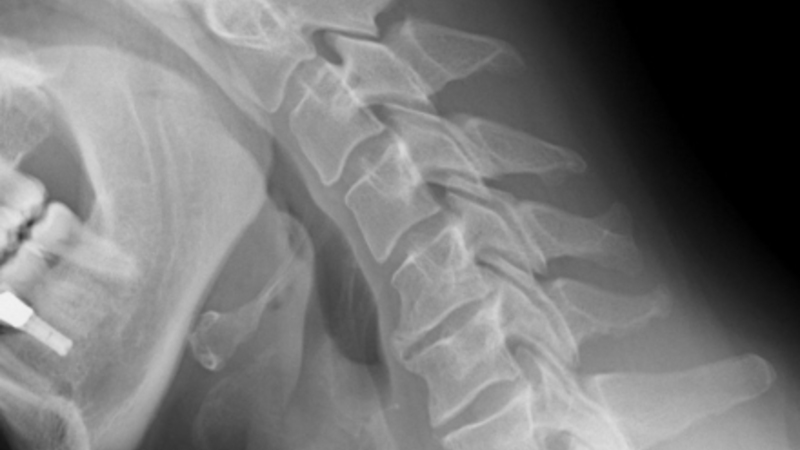

Costa del Sol sygehuset i Marbella er blevet pålagt at betale erstatning på 79.564 euro til en patient, der blev sendt hjem med en brækket nakke.

Den 48-årige bygningsarbejder havde været udsat for en ulykke i Estepona, hvor han blev ramt af to planker, der faldt ned over ham fra flere meters højde.

Manden faldt om i halv bevidstløs tilstand og kørt til en klinik i Estepona, som tilbød dækning via arbejdsgiverens privatforsikring. Manden blev bagefter overført til Costa del Sol Sygehuset, hvor en række tester og undersøgelser konkluderede, at han ikke fejlede noget. Han blev sendt hjem igen og fik besked på at gå til fysioterapi, indtil smerterne var forsvundet.

Men smerterne fortsatte, og på et tidspunkt kunne manden slet ikke bevæge den ene arm. En scanning på en privatklinik afslørede, at der var et brud i en halshvirvel efter slaget, og manden blev sendt til undersøgelse på Carlos Haya Sygehuset i Málaga, som bekræftede at, manden havde brækket nakken.

Der var imidlertid ikke meget at stille op, og den 48-årige bygningsarbejder har siden lidt af stiv nakke og kroniske smerter. Han er i dag tildelt fuld invalidepension.